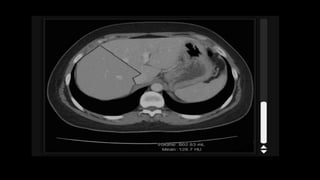

• On unenhanced CT normal liver parenchyma has homogeneous

density, which can vary between 55 and 65 HU.

• Exceeds that of the spleen by about 10HU.